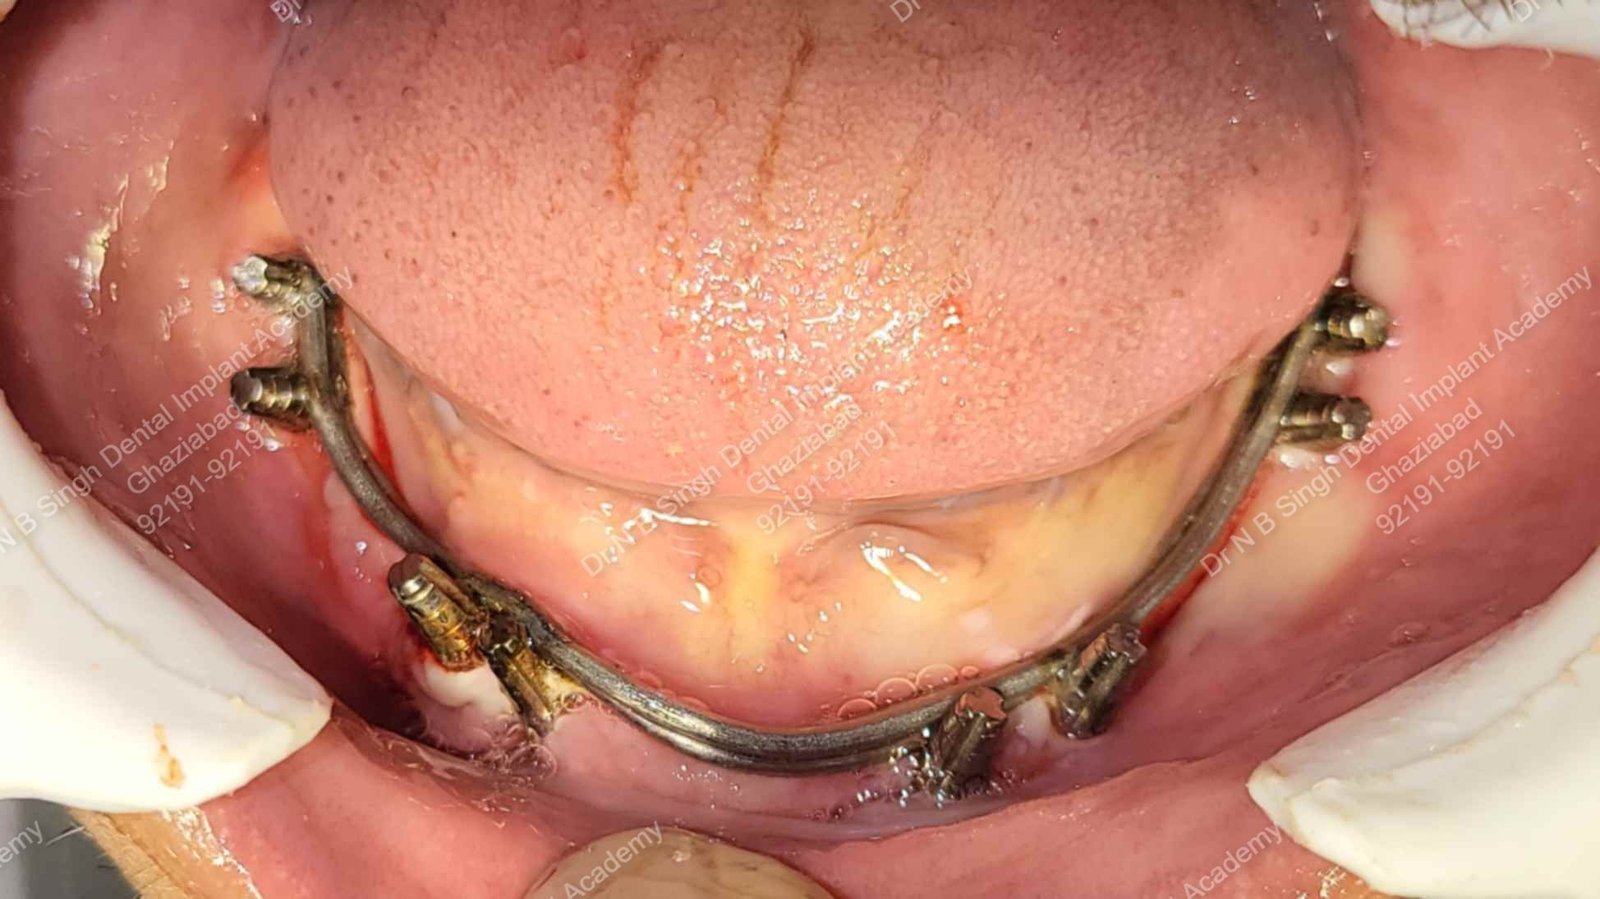

A009 Titanium 1.6 mm wire concretization [ intra oral welding ]